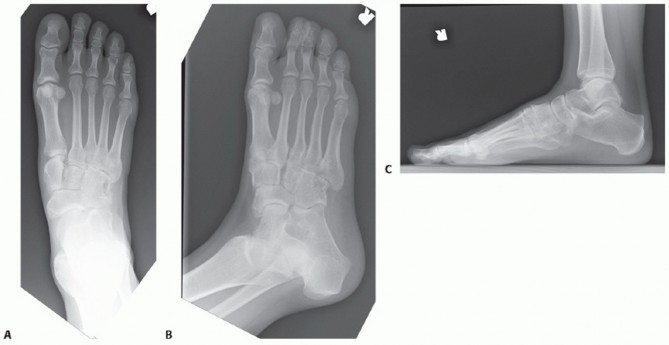

DEFINITION The distal chevron osteotomy has proven to be a reliable, reproducible method of bunion repair for…

DEFINITION Hallux valgus is a deformity of the forefoot characterized by progressive lateral subluxation of t…